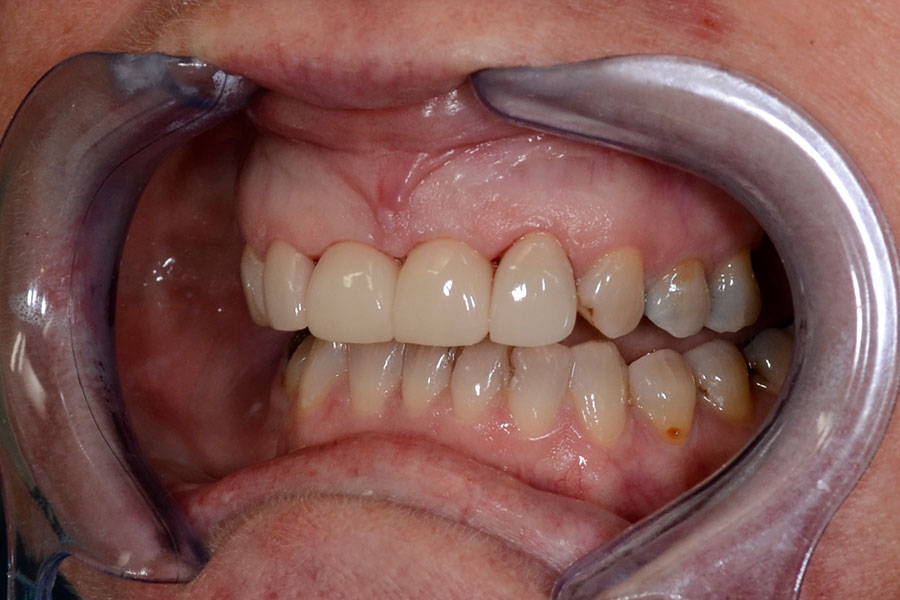

Christine had a crown on a root canal treated upper right central incisor that had a receding gum line.

Some of the white fillings on other front teeth were also stained. Pauline decided to have the crown replaced and ceramic veneers placed on other three adjacent teeth. The new crown is all ceramic and blends in more naturally with the veneers.